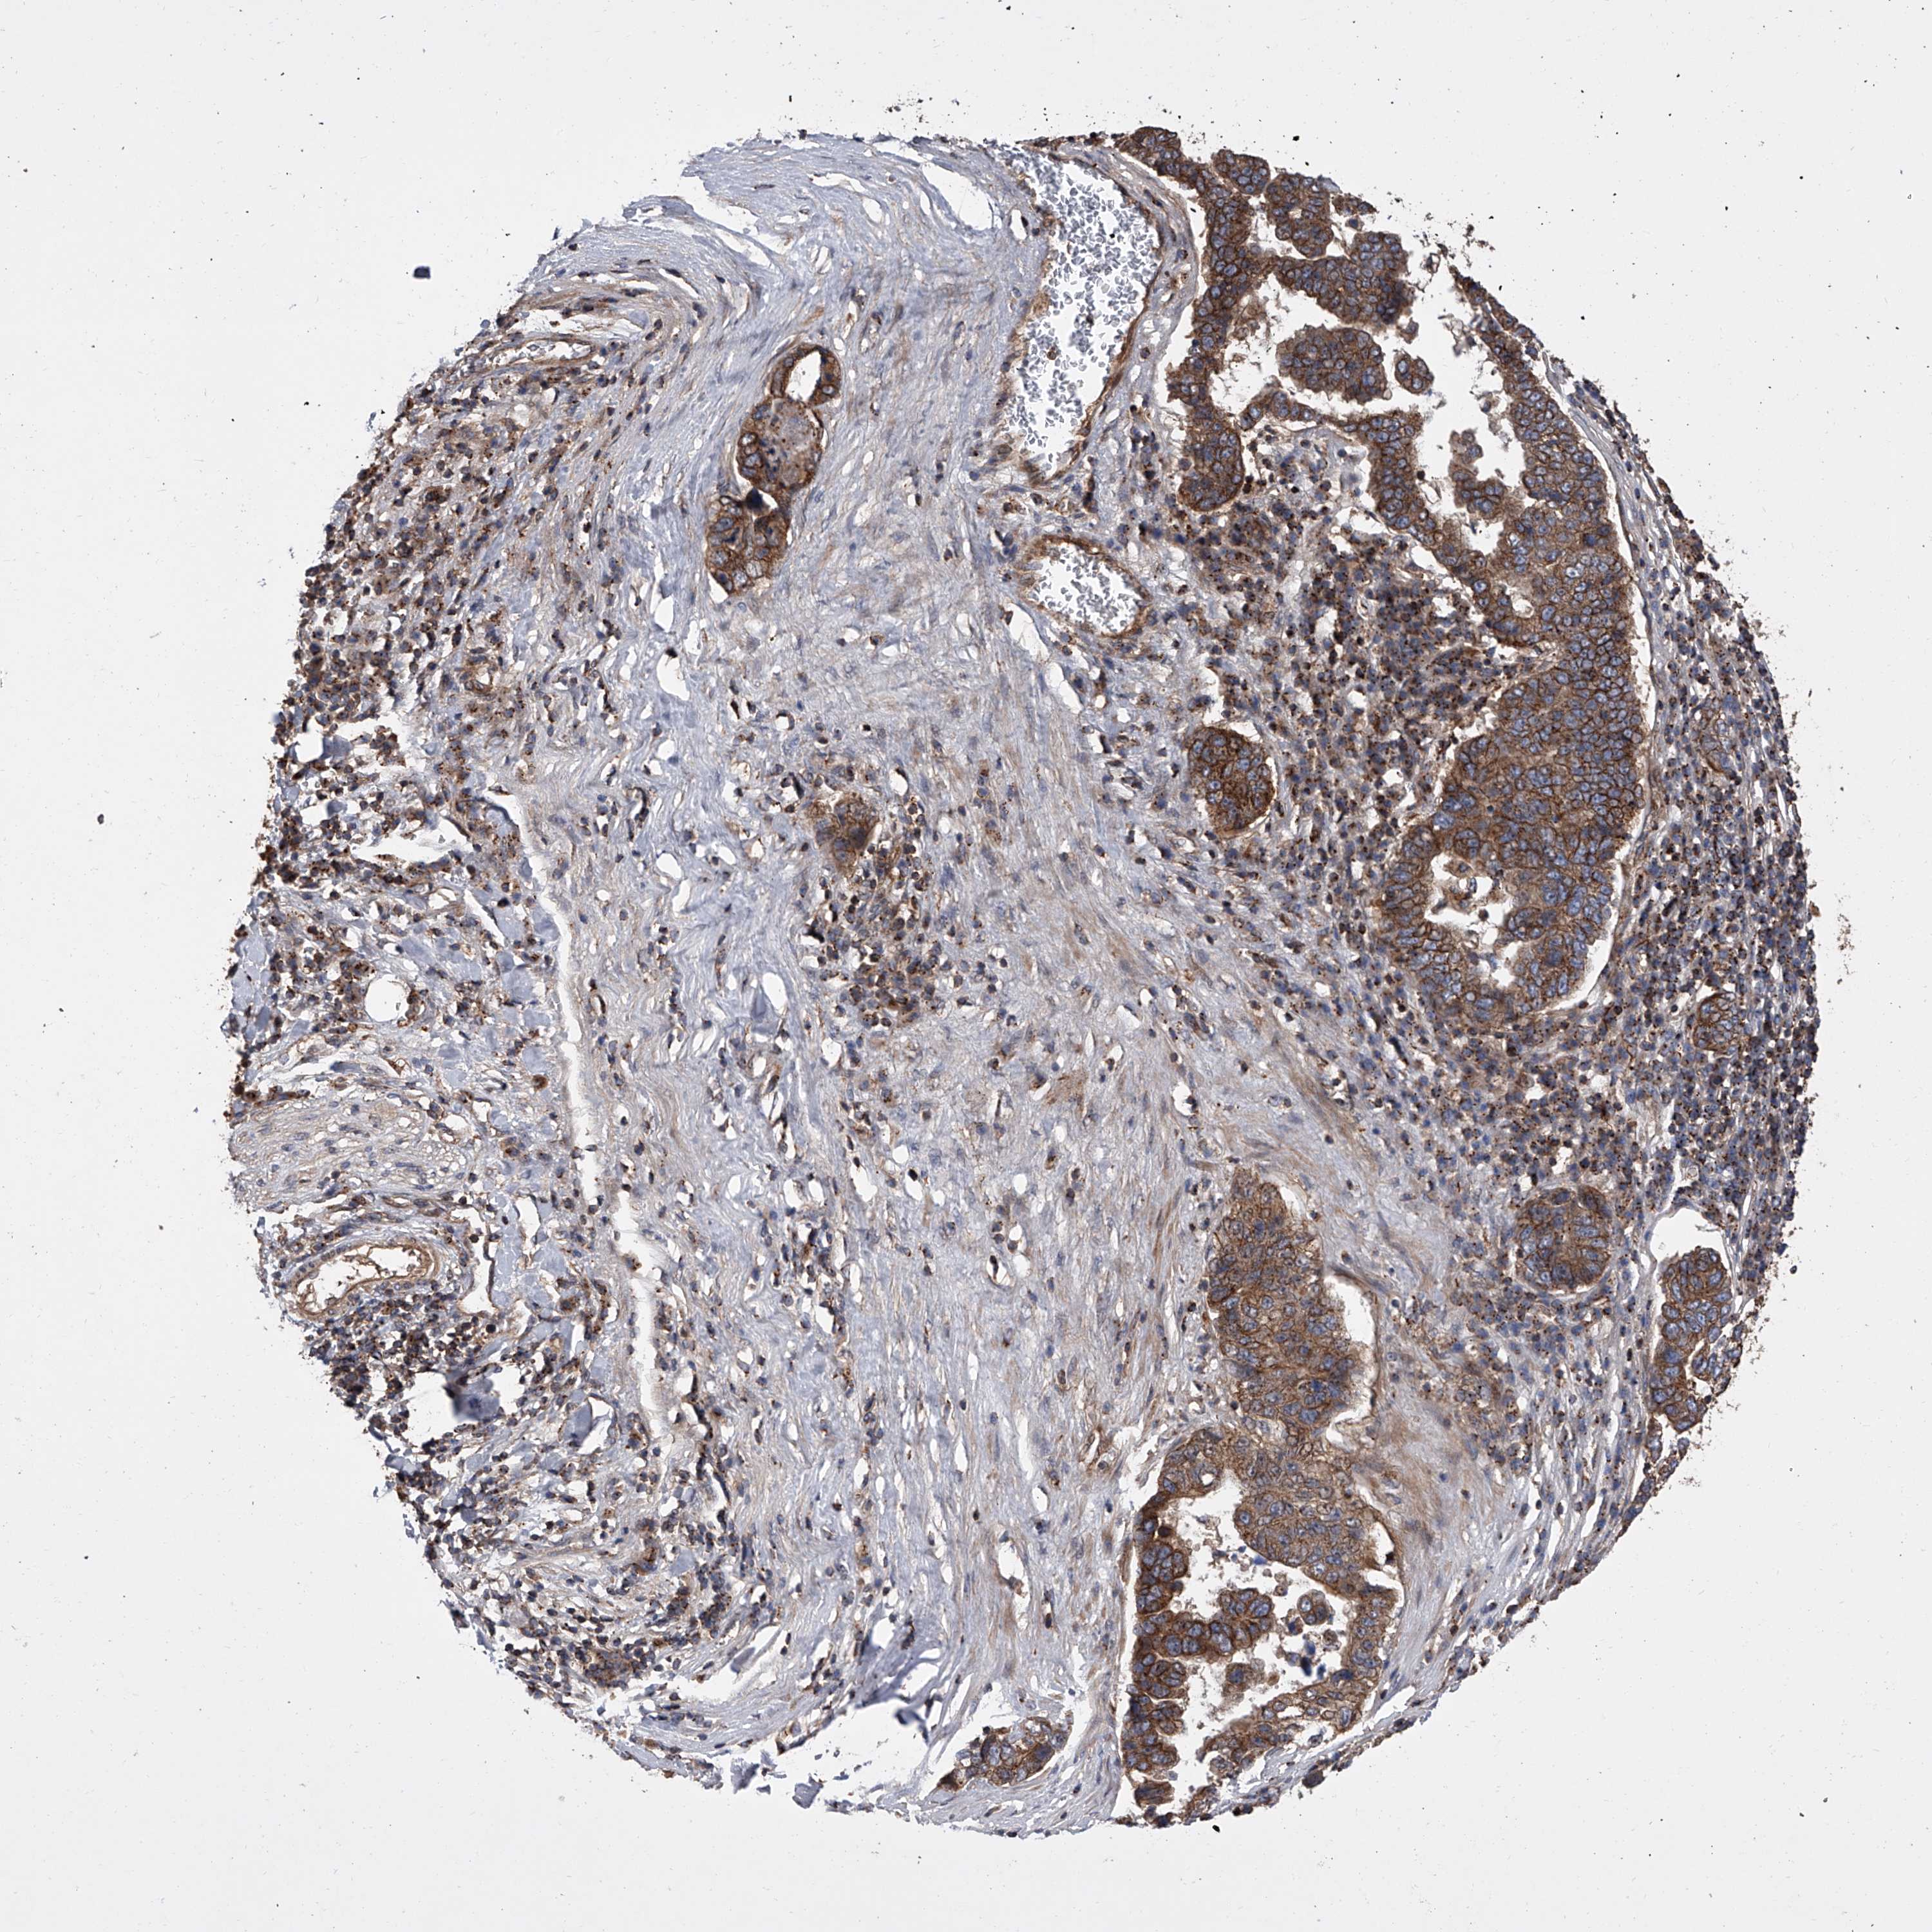

PANCREATIC CANCER - Protein expressioni

A mouse-over function shows sample information and annotation data. Click on an image to view it in a full screen mode. Samples can be filtered based on level of antibody staining by selecting one or several of the following categories: high, medium, low and not detected. The assay and annotation is described here.

Note that samples used for immunohistochemistry by the Human Protein Atlas do not correspond to samples in the TCGA dataset.

Antibody stainingi

Antibody staining in the annotated cell types in the current human tissue is reported as not detected, low, medium, or high, based on conventional immunohistochemistry profiling in selected tissues. This score is based on the combination of the staining intensity and fraction of stained cells.

Each image is clickable and will lead to virtual microscopy that enables deeper exploration of all samples and also displays staining intensity scores, fraction scores and subcellular localization as well as patient and tissue information for each sample.

Antibody HPA029286

Antibody HPA029289

Adenocarcinoma, NOS